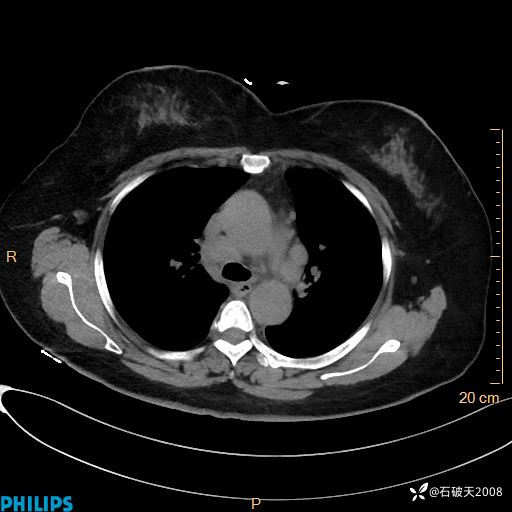

肺结节病?纵膈型肺癌?淋巴瘤?有点意思,欢迎围观

女 52岁 主 诉:咳嗽10余天,咳痰2天。

现病史:10余天前无明显诱因出现咳嗽,呈阵发性干咳,伴咽喉部发痒,无咽痛,无咳痰,无鼻塞、流涕、打喷嚏,无发热、畏寒、寒颤,无头痛、头晕,无胸闷、胸痛,无反酸、烧心,无腹痛、腹泻,无尿频、尿急,无皮疹等,在当地诊所求治,给予口服药物治疗(具体不详),病情无好转。遂在当地社区卫生服务中心开具口服药物治疗(具体不详),疗效欠佳。2天前出现咳痰,在我院门诊求治,行胸部CT提示肺部感染,建议住院,患者要求口服药物治疗,目前仍咳嗽、咳白色粘痰,白天量多,夜间自觉喉部喘鸣音,遂再次来院就诊,以“肺部感染”为诊断收入院。发病以来,神志清,精神可,饮食可,夜间睡眠差,大小便正常,近期体重无明显变化。

肺窗

纵隔窗